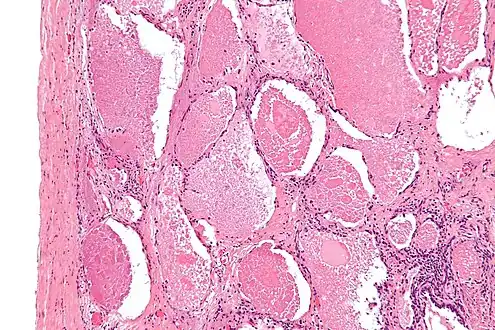

Lung washings or tissue for histopathologic analysis are most commonly obtained using bronchoalveolar lavage and/or lung biopsy.[12] Characteristic biopsy findings show filling of the alveoli (and sometimes terminal bronchioles) with an amorphous eosinophilic material, which stains strongly positive on PAS stain and the PAS diastase stain. The surrounding alveoli and pulmonary interstitium remain relatively normal.[13] Electron microscopy of the sample, although not typically performed due to impracticality, shows lamellated bodies representing surfactant.[14] An alternative diagnosis with similar histomorphologic findings is Pneumocystis jirovicii pneumonia.[14]

Lung washings characteristically yield a fluid which is "milky"composition. Under the microscope, samples show 20-50 micrometer PAS-positive globules on a background of finely granular or amorphous PAS-positive material. There is typically a low numbers of macrophages and inflammatory cells (although this is variable).[13][14]